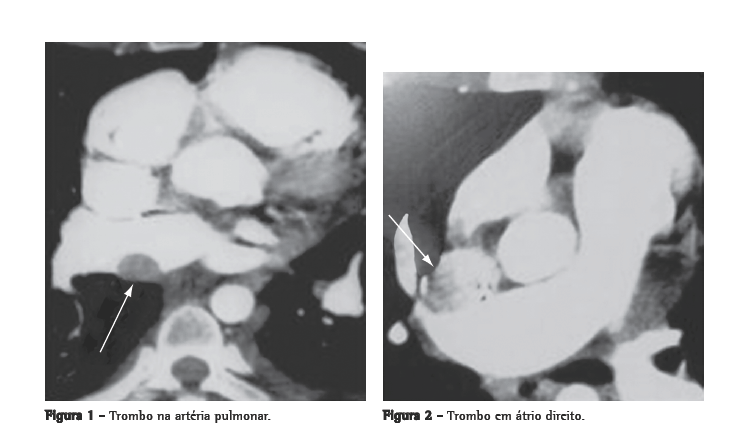

A paciente recebeu tratamento para esquistossomose e foi transferida para hospital de referência. Foi realizada cintilografia pulmonar, que mostrou alta probabilidade de TEP, com hipoperfusão no lobo superior direito e hipoperfusão em pulmão esquerdo, sem alterações ventilatórias. A angiotomografia computadorizada (Figuras 1 e 2) revelou trombos em artéria pulmonar e átrio direito. A pesquisa de dímero-D pelo método qualitativo (Diagnostica Stago, Asnières-Sur-Seine, França) resultou maior >8.000 ng/mL e por meio de um ensaio imunoenzimático (rapid ELISA Vidas d-dimers; Biomérieux, Marcy l'Etoile, França), 5.154,02 ng/mL; ponto de corte, 500 ng/mL.